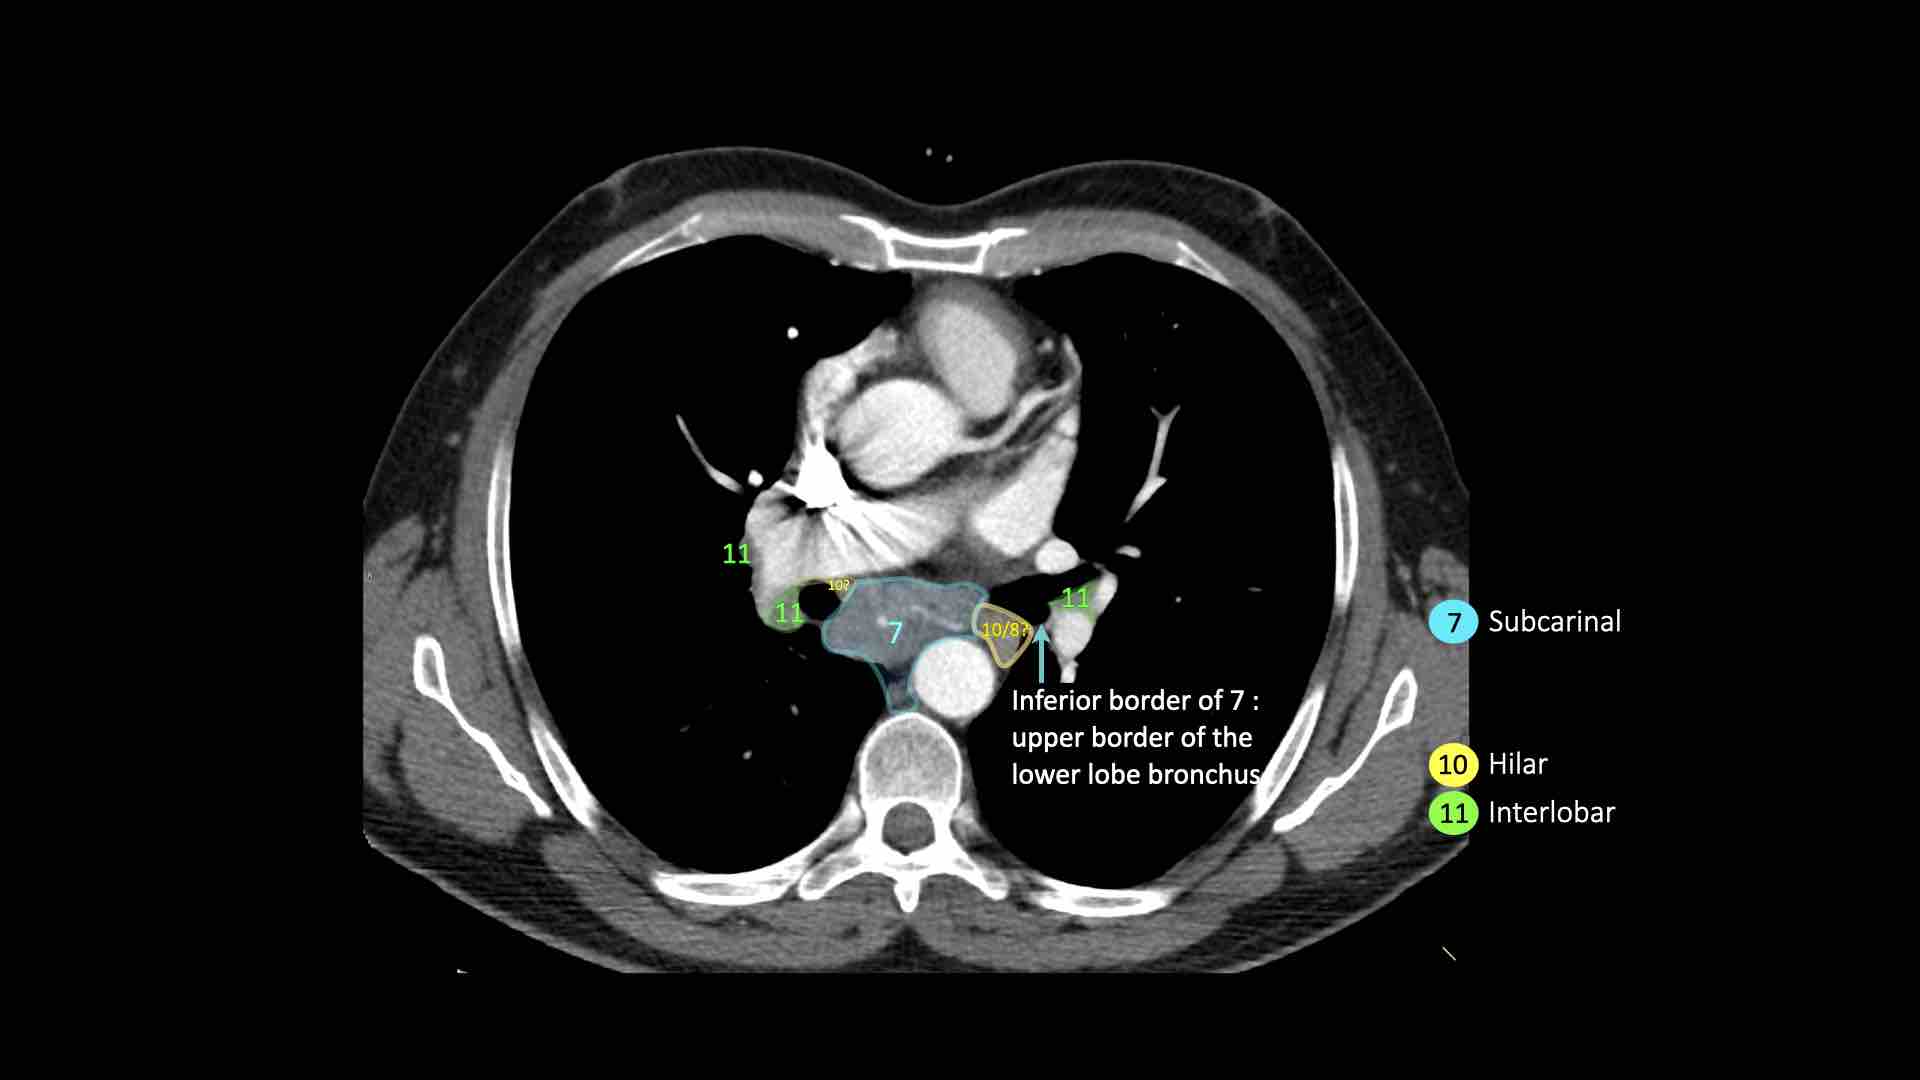

7. Hạch dưới carina

Các hạch này nằm ở phía dưới carina khí quản, nhưng không liên quan đến phế quản thùy dưới hoặc các động mạch trong phổi.

Bên phải, chúng trải dài xuống đến bờ dưới phế quản trung gian.

Bên trái, chúng trải dài xuống đến bờ trên phế quản thùy dưới.

Bên trái là hạch dưới carina nhóm 7 nằm bên phải thực quản.

10. Hạch rốn phổi

Hạch rốn phổi là các hạch thùy gần, nằm ở phía xa so với nếp gấp màng phổi trung thất và các hạch kề phế quản trung gian bên phải.

Các hạch từ nhóm 10 đến 14 đều là hạch N1, vì chúng không nằm trong trung thất.